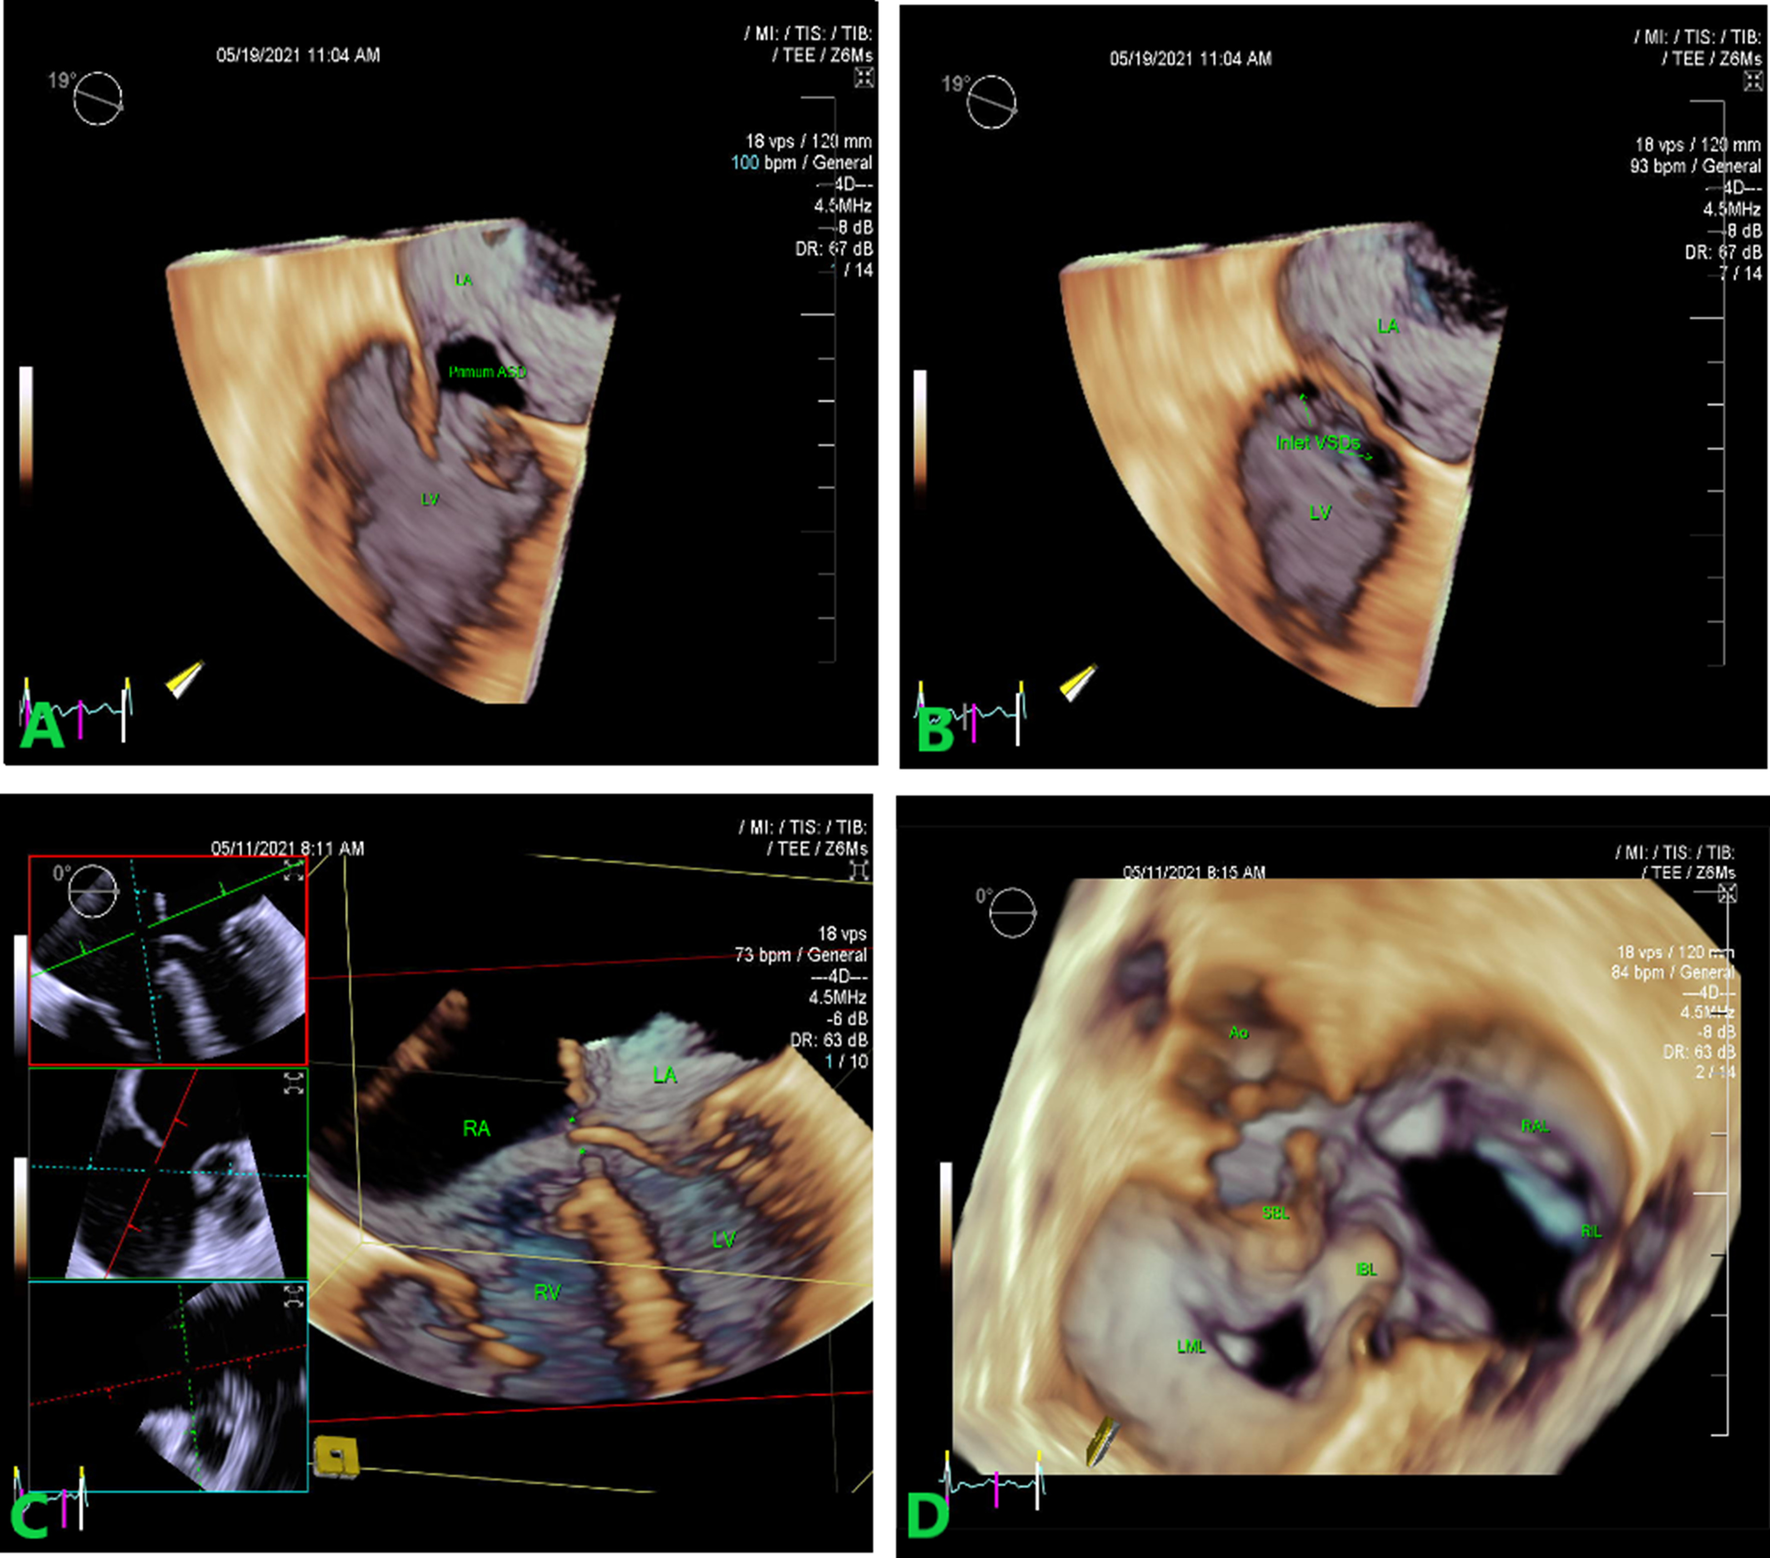

Fig. 3

A AVSD—AV septum deficiency. 3D TEE. 3D high volume, high resolution, and single-beat sample, cropped form the front using the green plane adjustment reveals the AV septum deficiency (asterisk). B 3D echocardiography of the primum atrial septal defect—left sided en face view. C Inlet VSDs. LV en face view of inlet interventricular septal defects. Smaller defects (asterisks) in membranous part of IVS. D RT3D TEE left atrial perspective view of the common atrioventricular valve. The common AV valve is with one annulus and two orifices. Both the superior and inferior bridging leaflets are seen. Triangle appearance of the left sided orifice and the elliptic shape of right sided AV orifice. The common valve consist of five leaflets—superior bridging leaflet (SBL), inferior bridging leaflet (IBL), left mural leaflet (LML), right mural or inferior leaflet (RML) and right anterior or superior leaflet (RAL). AVSD atrioventricular septal defect, TEE transesophageal echocardiography, VSD ventricular septal defect, AV atrioventricular